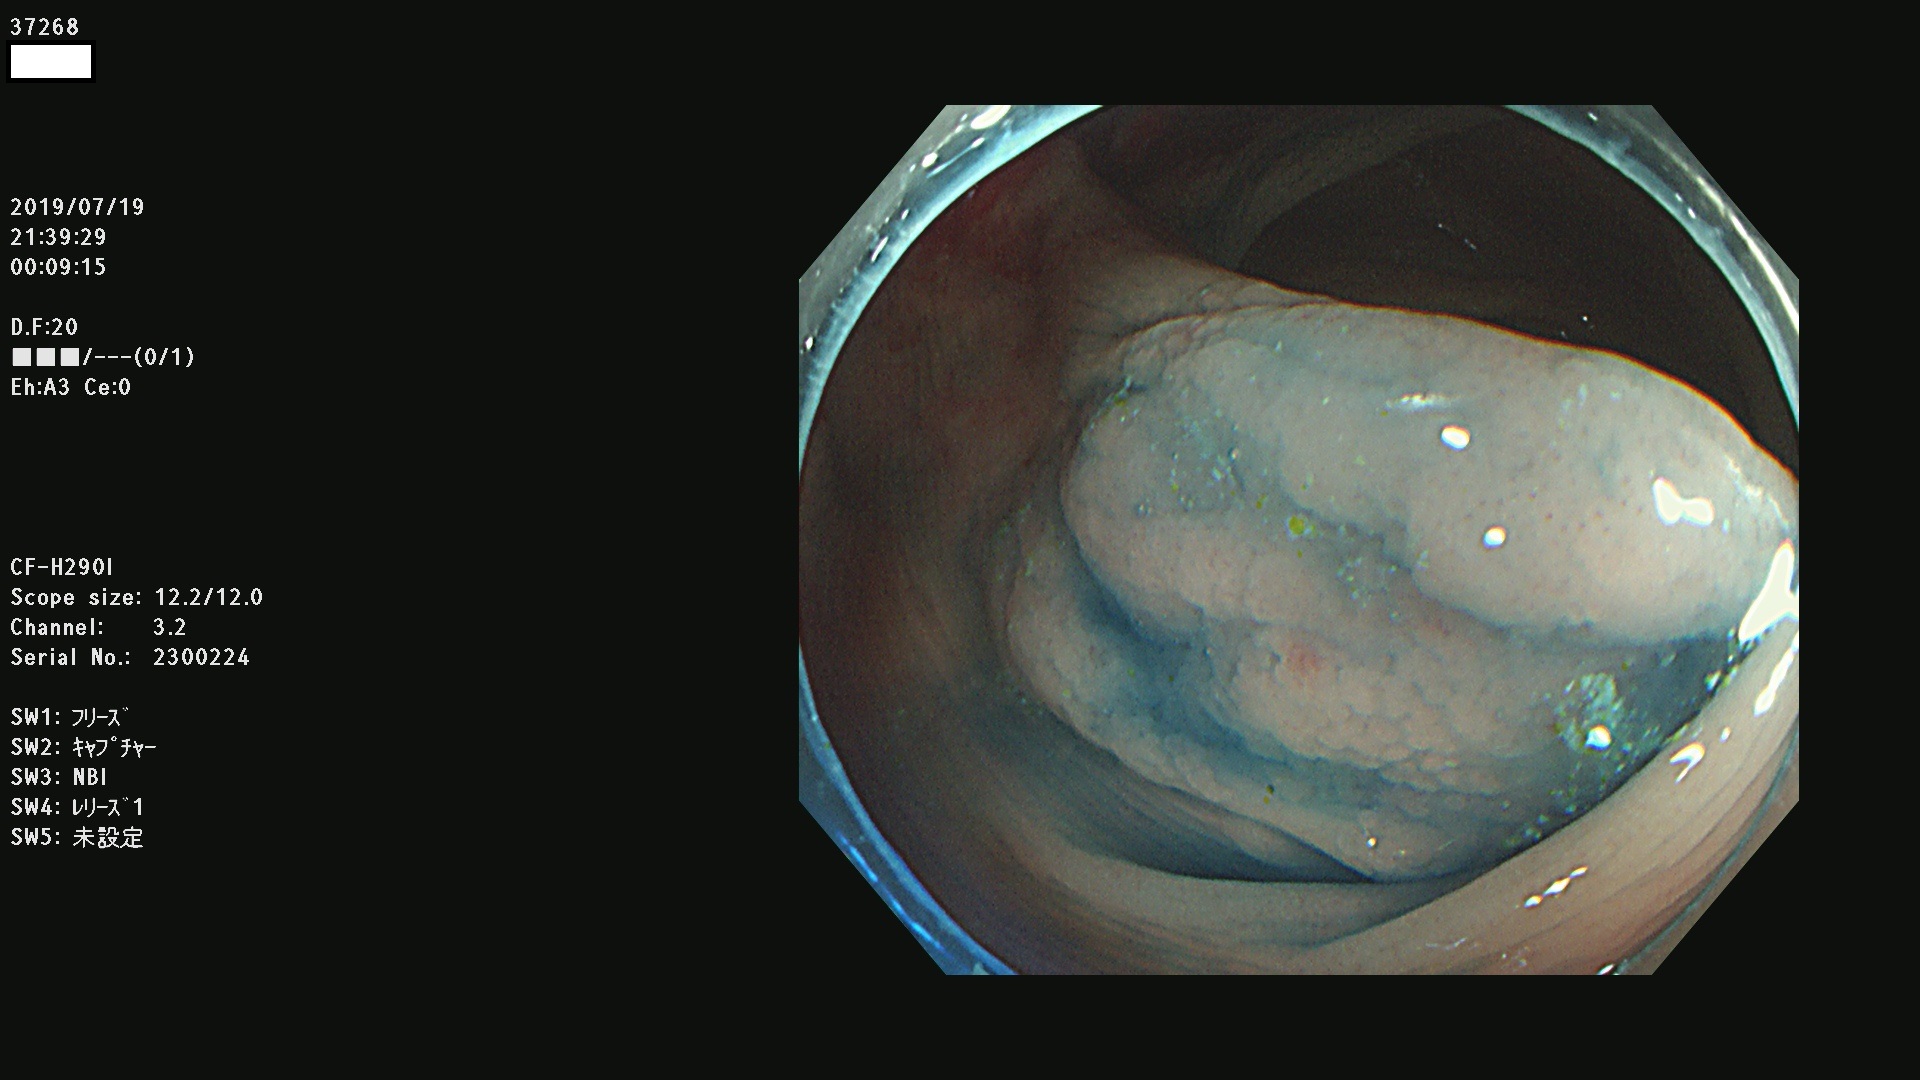

37200 37203 37204 37207 37208 37209 37210 37211 37212 37213 37214 37215 37216 37217 37220 37221 37222 37224 37225 37228 37229 37230 37232 37233 37234 37235 37236 37238 37241 37242 37243 37244 37245(SSAPのみ) 37247 37249 37250 37251 37252(SSAPのみ) 37254 37256 37257 37258 37259 37260(SSAPのみ) 37261(SSAPのみ) 37262 37263 37264 37265 37266 37267 37268(SSAPのみ) 37269 37271 37273 37274 37276 37277 37278 37279 37280 37281 37282 37284(SSAPのみ) 37285 37286 37288 37289 37290 37292 37293 37295 37296 37297(SSAPのみ)

発見困難で危険性の高い平坦型病変(上記100名より抽出)